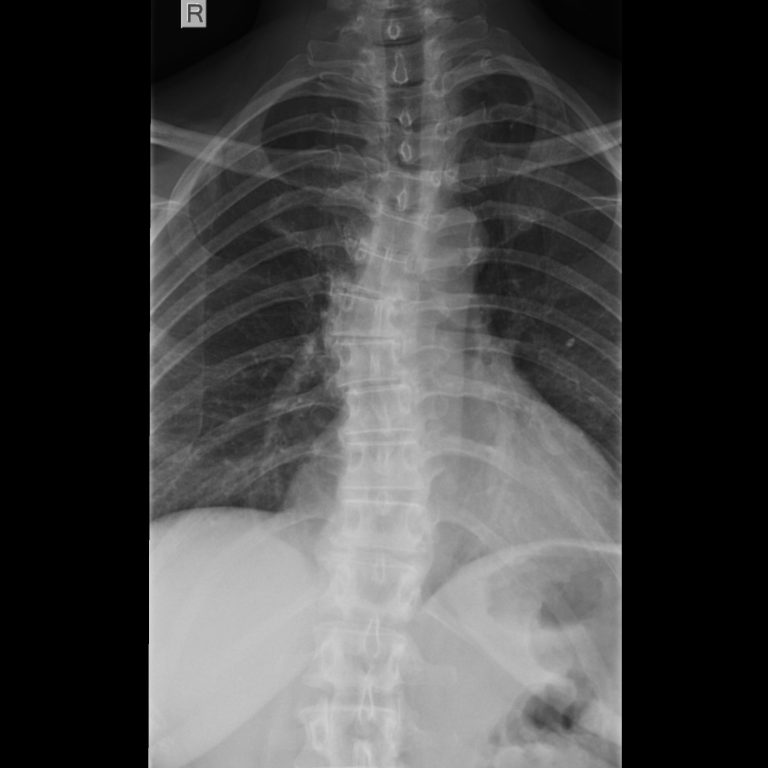

Skoliose

(Achsabweichung der Wirbelsäule):

Eine Achsabweichung der Wirbelsäule entsteht in aller Regel während des Wachstums. In dieser Phase ist eine regelrechte Behandlung der Skoliose von entscheidender Bedeutung, da sich nur hier die Ausprägung der Abweichung noch beeinflussen lässt.

Die Behandlung erfolgt nach Ausschluss anderer zugrunde liegender Erkrankungen in der Regel konservativ mittels Sport, individueller Kräftigung der Rumpfmuskulatur, Haltungsschulung oder spezieller Krankengymnastik nach Katharina Schroth. Bei besonders ausgeprägten Deformitäten steht die konservativ stationäre Behandlung in einer spezialisierten Skolioseklinik oder auch die Behandlung mittels eines Korsetts zur Verfügung. Eine operative Therapie ist meist nicht erforderlich.

Wenn Sie es wünschen, untersuchen wir, ob bei Ihnen oder Ihrem Kind eine behandlungsbedürftige Skoliose vorliegt, und besprechen zusammen, welche weiteren Schritte gegebenenfalls unternommen werden können, um die bestmögliche Funktion Ihrer Wirbelsäule zu erreichen.